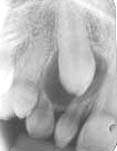

Lesões Maxilo-Mandibulares